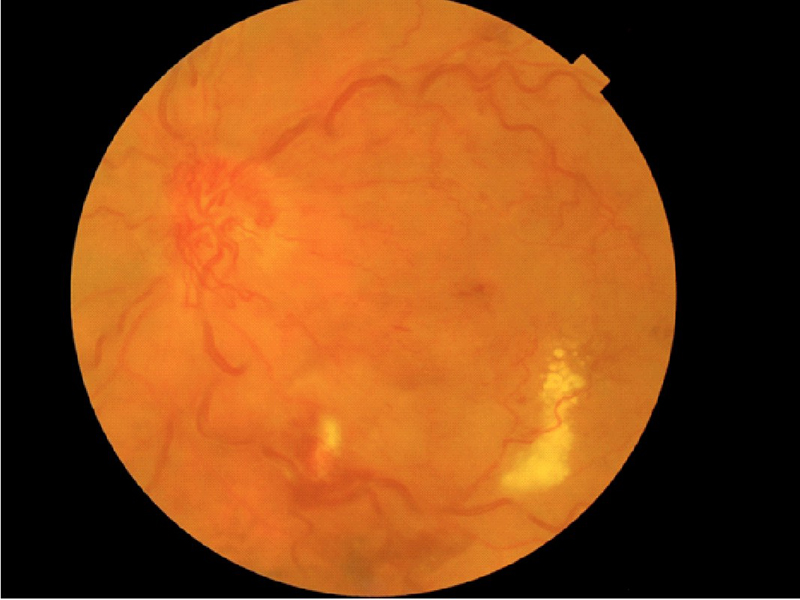

En la

Figura 10 se muestra una oclusión de vena central de la retina de 1 año de evolución, con importante tortuosidad, colaterales papilares, edema macular y exudación lipídica crónica. En la imagen de OCT del mismo paciente (

Figura 11) se aprecia un gran engrosamiento retiniano con quistes intraretinianos y desprendimiento seroso retiniano. En la parte de la izquierda de la imagen puede verse tanto la hialoides como la presencia de una membrana epiretiniana.

Figura 10. Oclusión de la vena central de la retina después de 1 año de evolución: importante tortuosidad vascular, colaterales papilares, edema macular y exudación lipídica crónica.

Figura 11. OCT del paciente de la Figura 10: gran engrosamiento retiniano con quistes intraretinianos y desprendimiento seroso retiniano. En la parte izquierda de la imagen se ven tanto la hialoides como una membrana epirretiniana.